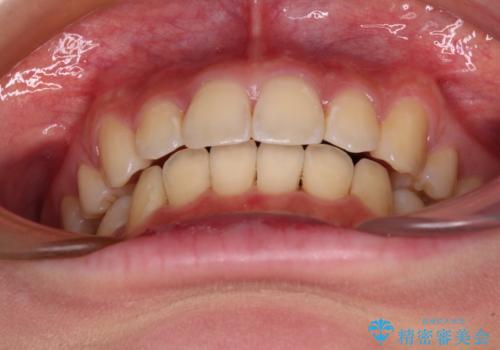

上下左右4本抜歯する場合には、通常2年から2年半ほどの期間を要しますが、僅か1年半で終了することができました。